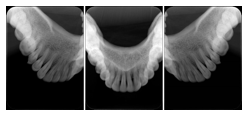

2. A patient requests cosmetic surgery to enhance their facial appearance. The case requires consultation between an orthodontist in New York and an oral surgeon in California. The cephalometric series of 2D projections constructed from the volumetric CT data that is used for the discussion is arranged by a Structured Display for transfer between the two practitioners.

Cephalometric Series Structured Display

Figure OO-2. Cephalometric Series Structured Display